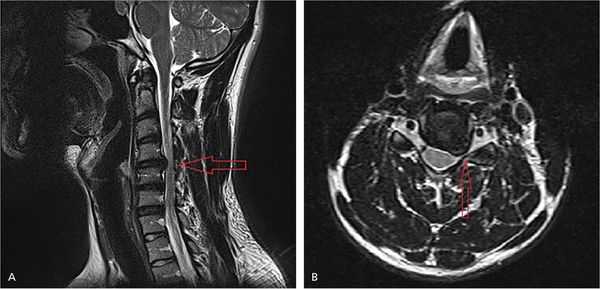

На рисунке А (вид сбоку) стрелкой указана локализация грыжи межпозвонкового диска на уровне шейных С4-С5 позвонков. Грыжа выступает в позвоночный канал и смещает или сдавливает спинной мозг. На рисунке В (вид сверху) стрелкой отмечена та же грыжа, которая выступает влево и сдавливает нервный корешок.